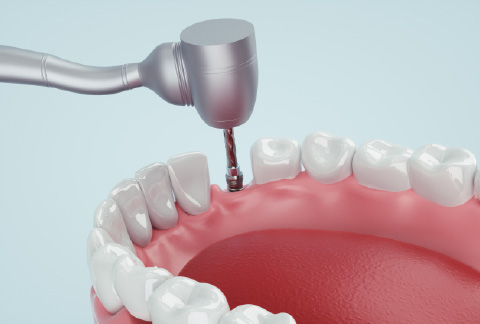

インプラント治療とは、失ってしまった自分の歯の代わりに、人工の歯根を顎の骨に埋め込み、その上に人工の歯を作製して噛み合わせを回復する治療法です。

2- 一次手術

ふじなわ歯科医院では、仮歯用のインプラントを埋入することによって、本インプラントが定着するまでの期間、歯がなかったり入れ歯を入れることなくお過ごしいただけるようにしております。